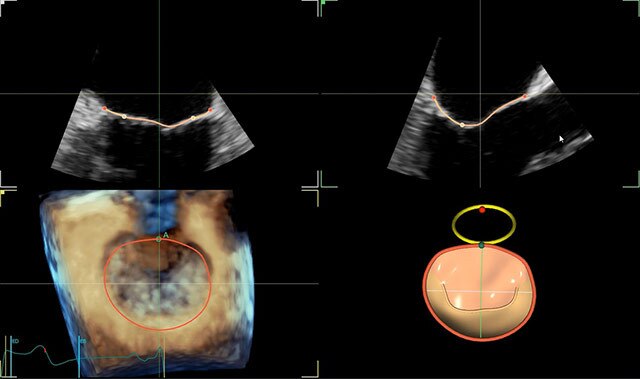

4D Auto MVQ*

4D Auto AVQ*